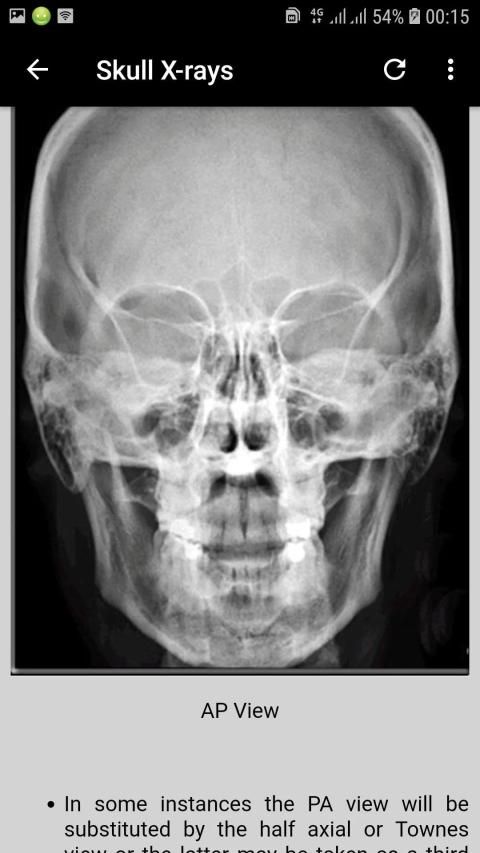

Interpretation of Skull, paranasal sinuses, orbit, chest, abdomen, urogenital tract (pelvis), and musculoskeletal x-rays.

Interpretasi tengkorak, sinus paranasal, orbit, dada, perut, saluran urogenital (pelvis), dan x-ray muskuloskeletal